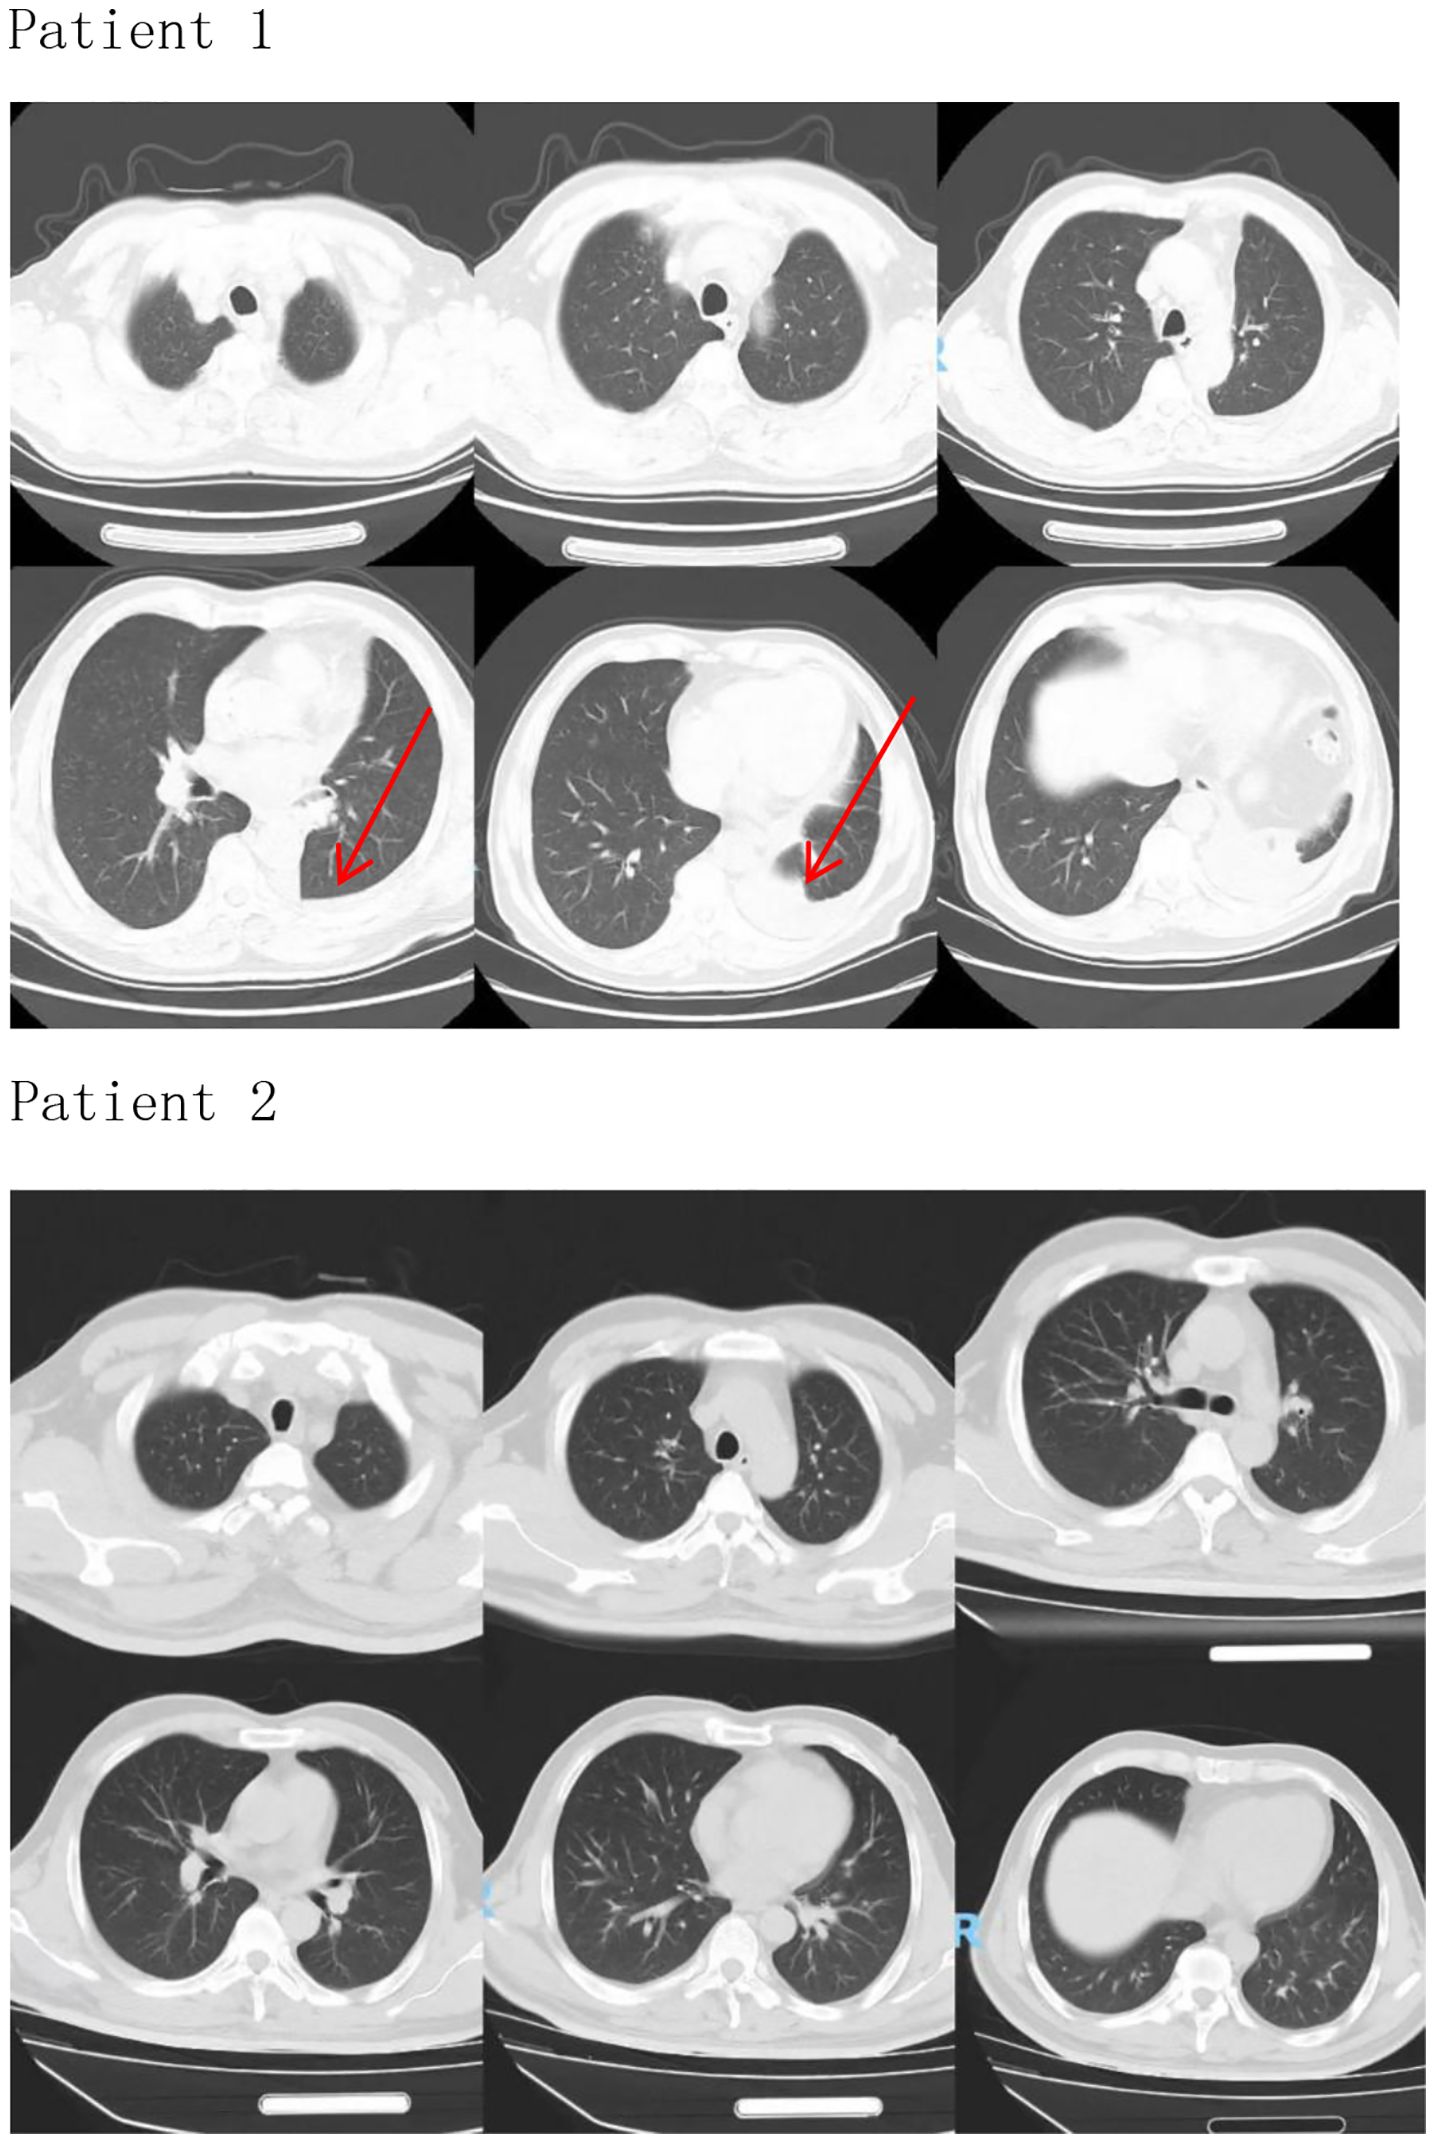

4. Literature Consensus: Current guidelines (NCCN, ESMO) recognize MG as a risk factor for ICI cardiotoxicity but not an independent cause of myocarditis. Fatal overlap syndromes (e.g., IM3OS) occur exclusively after ICI exposure in such patients. This aligns with Pathak et al.’s finding that pre-existing autoimmune conditions (like MG) potentiate ICI toxicity but require the inciting agent (tislelizumab) to trigger multi-organ autoimmunity. Severe myocardial injury resulted in a fatal outcome. Two patients were admitted to the hospital to check lung imaging, which did not show obvious abnormalities (Figure 1, Patient 1 and Patient 2). Only Patient 1 underwent left lower lobectomy. Infection indicators were normal, excluding intestinal infections, lung infections, lung cancer, and intestinal cancer as causes of fatigue and other symptoms. Therefore, the causal relationship between tislelizumab and immune-associated myocarditis in these patients is very likely.

CT scans of two patients showing their thoracic regions. For Patient 1, six images highlight areas with red arrows indicating possible abnormalities in the lungs. Patient 2's six images show clear lung scans without marked anomalies.

Figure 1. Patient 1 (The arrow indicates the left lower lobectomy site on the CT image.), Patient 2.